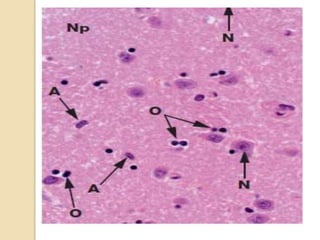

Neuronal populations of

DNTs:

•mature neurons

•may show cytological

anomalies

• no dysplastic ganglion cells

Cortical topography

•Limits of tumour often coincide

with that of the cortex.

•May have disordered neuronal

migration